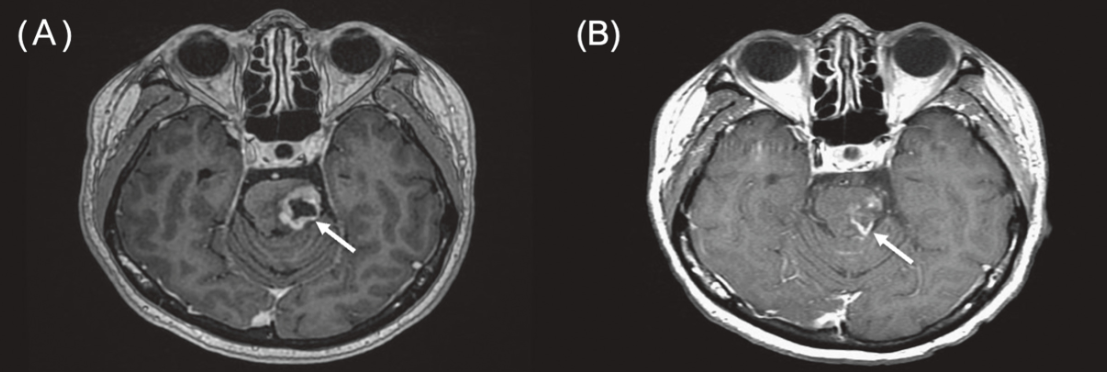

近期,一项发表于《Critical Reviews in Oncology/Hematology》的Meta分析,系统评估了硼中子俘获疗法(BNCT)治疗局部复发性头颈癌(LRHNC)的疗效与安全性。